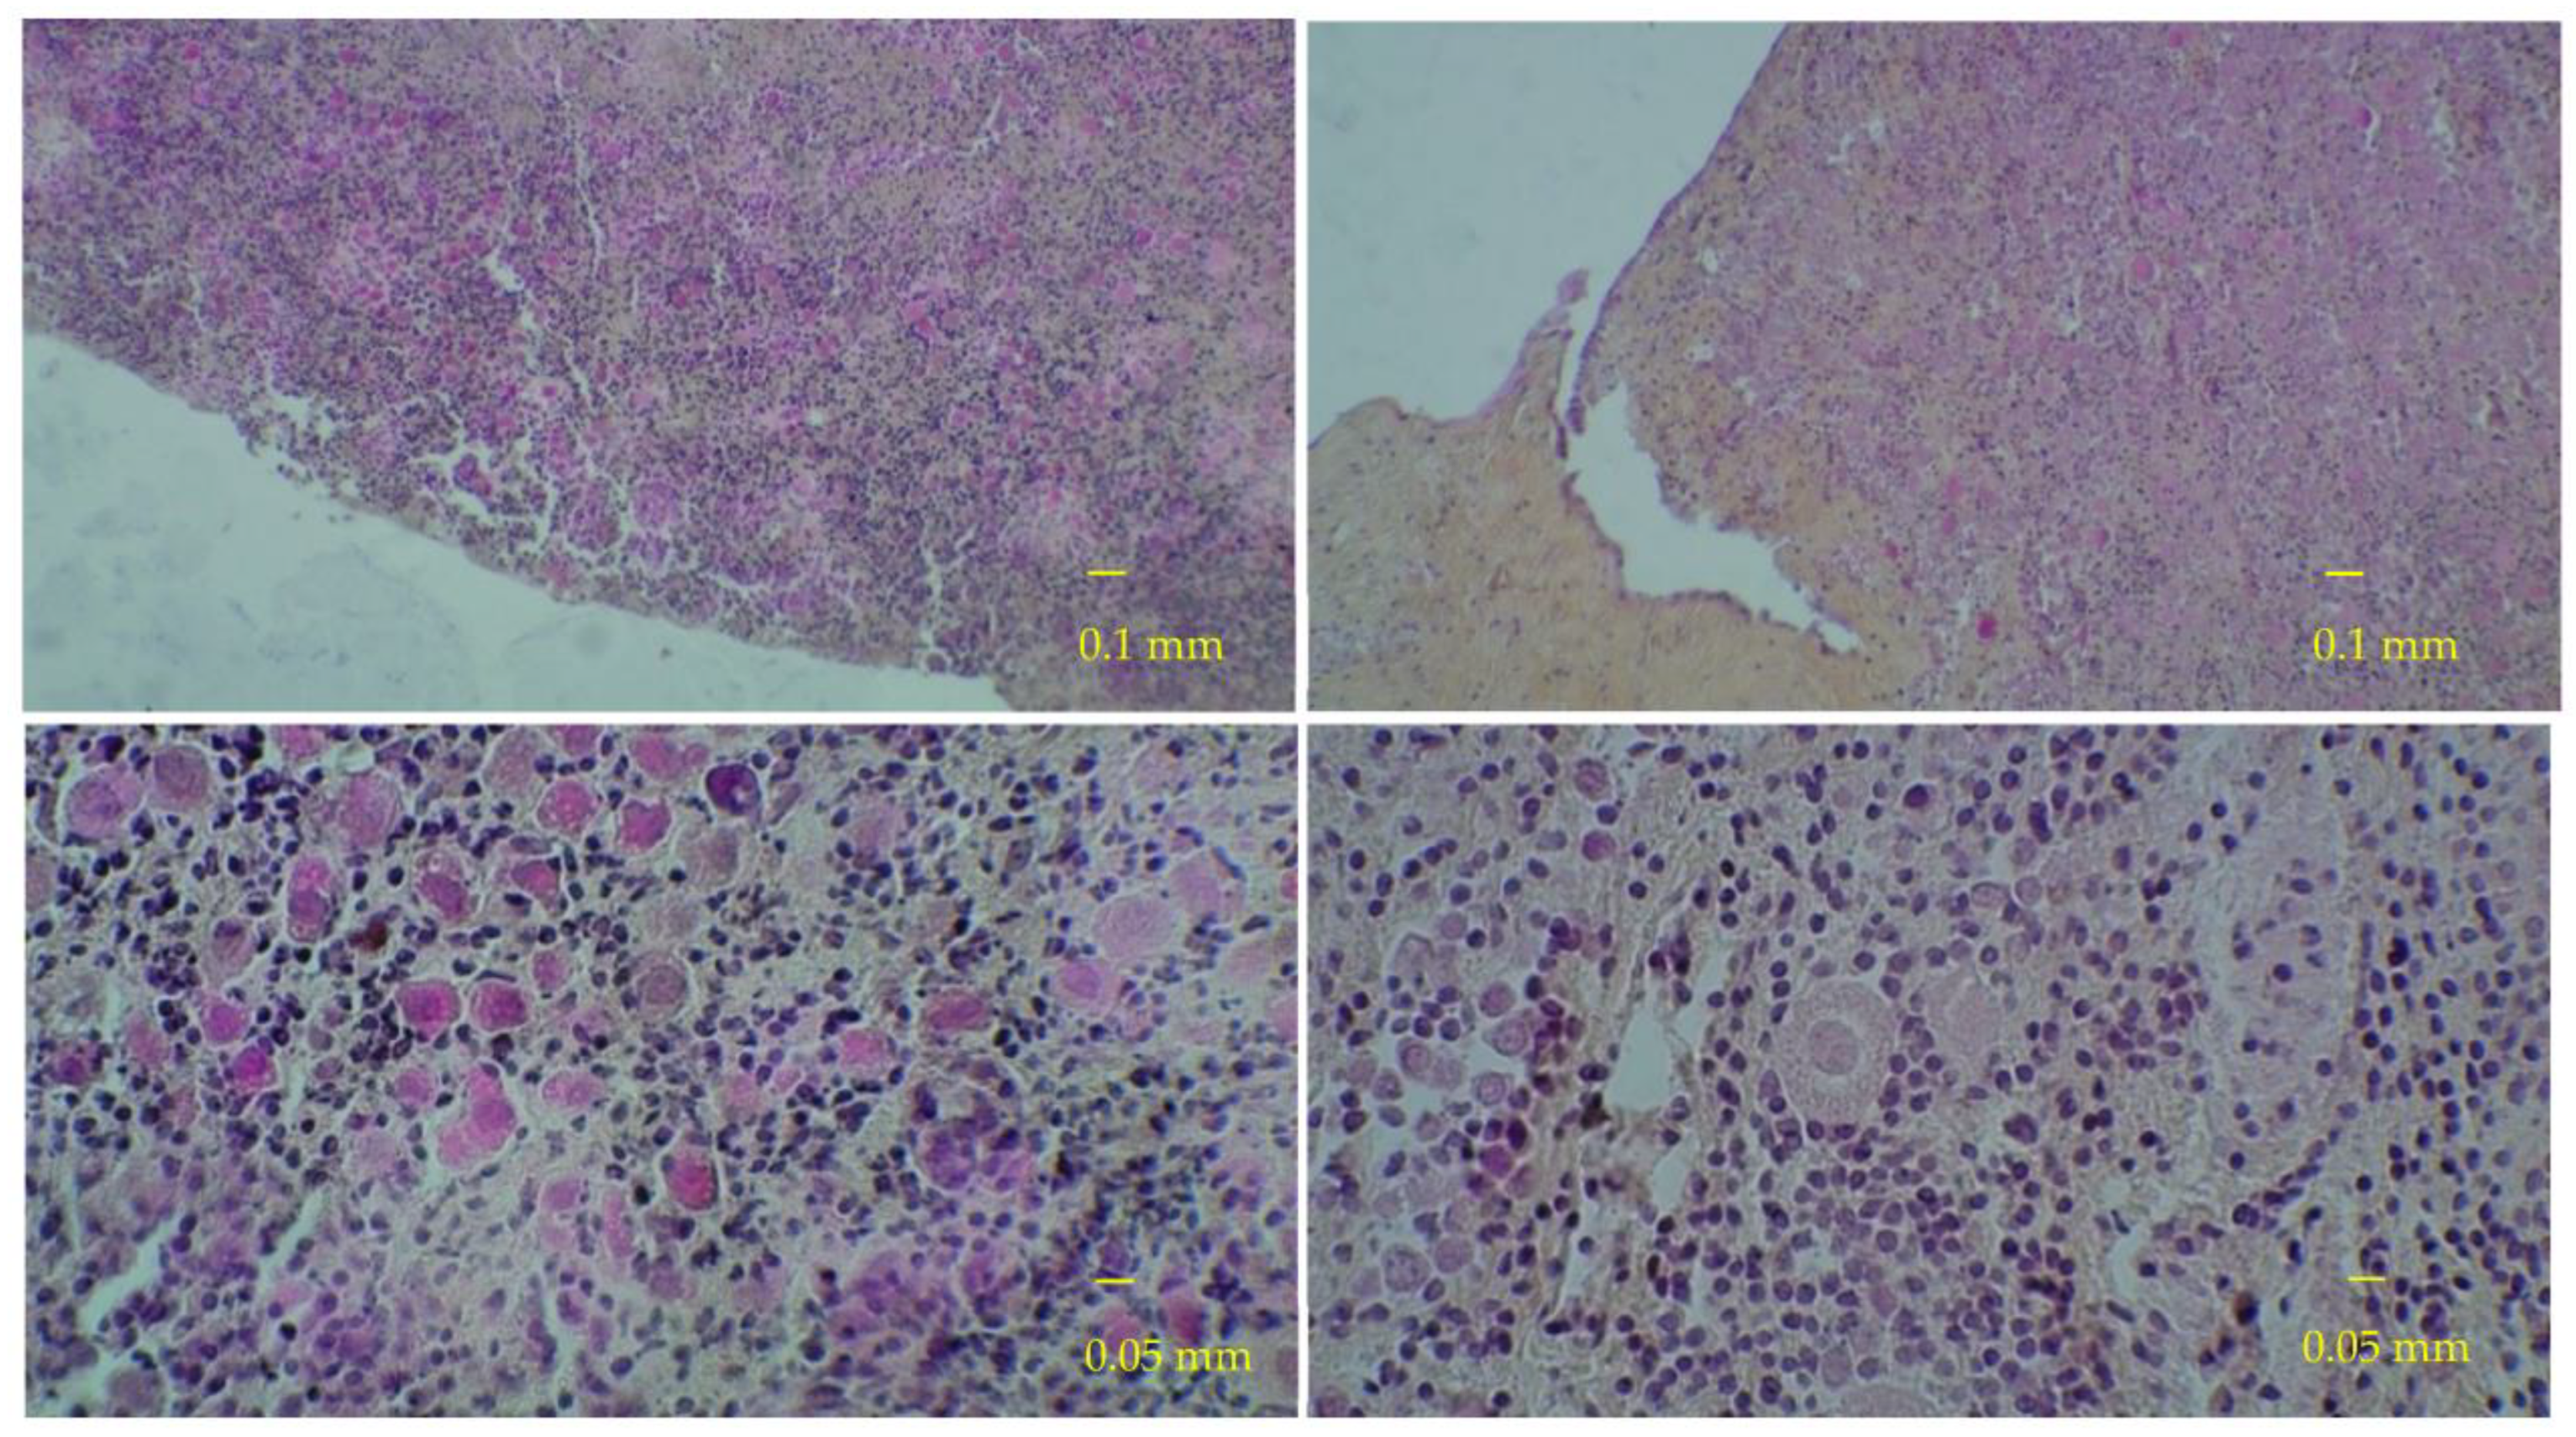

2.4. Histological Analyses

3. Results

3.1. Results of the First Set of Analyses with Intact Follicles as Denominator

3.2. Results of the Second Set of Analyses with All Present Follicles as Denominator

3.3. Immunostaining for Cell Apoptosis